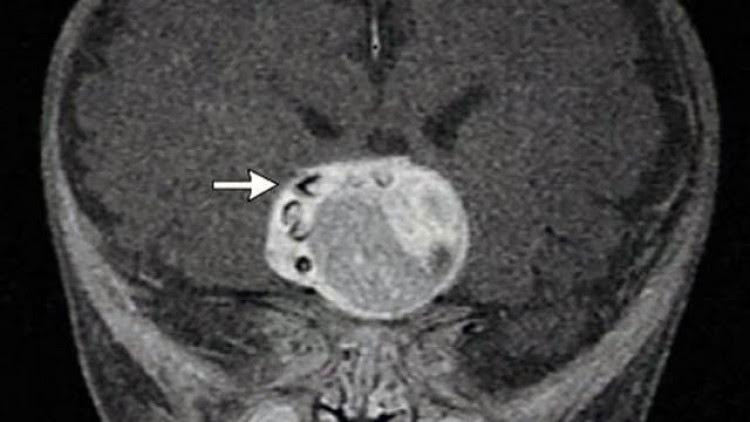

В Мериленд лекари извършиха необичайна операция, премахвайки няколко зъба, които са порастнали в мозъка на четиримесечно бебе. Това съобщава британското издание DailyStar.

По думи на лекарите се оказало, че бебето има рядък вроден доброкачествен мозъчен тумор, наречен краниофарингиома.

Специалистите са сигурни, че туморът е провокиран от пораснали зъби. Учените смятат, че той се формира от същите клетки като зъбите.